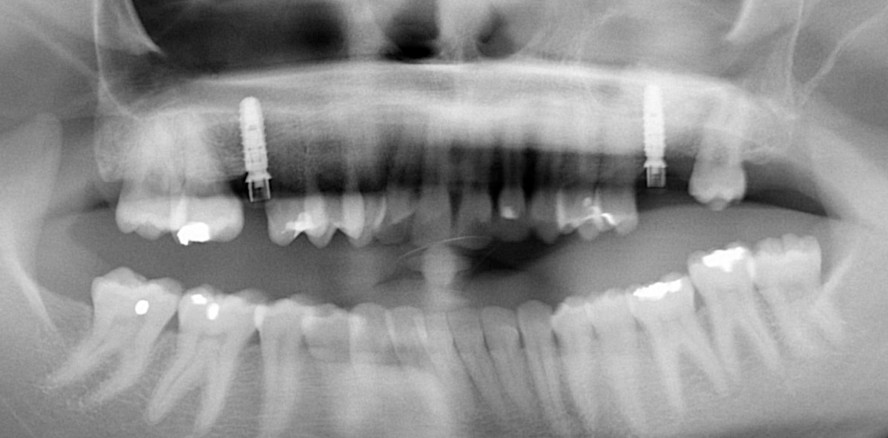

Eine 28-jährige Patientin kam, nachdem ihr die Seitenzähne 16, 26, 27 vor mehr als fünf Jahren alio loco extrahiert worden waren, zur Weiterbehandlung in unsere Praxis. Sie wünschte sich die Rekonstruktion der zahnlosen Kieferbereiche mit Implantaten. Bei der intraoralen Erstbefundung zeigte sich, dass das Fehlen des Zahns 16 eine mesiale Neigung des Zahns 17 initiiert hatte und der interproximale Raum verringert war. Bei der Röntgenaufnahme (OPG) wurden sowohl die Mesioangulation von 27 als auch mehrere kleinere Zahnfüllungen diagnostiziert. In Regio 16 und 26 war aufgrund der vertikalen krestalen Knochenresorption und der Sinuspneumatisierung eine deutliche Reduktion der Knochenhöhe erkennbar. Für eine stabile Insertion der Implantate waren Maßnahmen zum Knochenaufbau der Kieferhöhle erforderlich. Die Entscheidung fiel aufgrund der Bildgebung eines DVT-Scans mit erkennbarer Restknochenhöhe von unter 4 mm auf den externen Zugang zur Kieferhöhle. Der Sinusboden musste mehr als 3 mm eleviert werden, wobei die für den Abbau ursächliche Pneumatisierung rückgängig gemacht wurde. Im vorliegenden Fall entschieden wir uns für ein zweizeitiges Vorgehen, da die erreichbare Primärstabilität maßgeblich von der präoperativen Knochenhöhe beziehungsweise Knochenqualität abhängig ist.

Nach achtmonatiger Heilungsphase wurden eine intraorale Röntgenaufnahme und ein DVT angefertigt. Das Röntgenbild zeigte einen ausreichend hohen regenerierten Knochen an der transplantierten Stelle. Neun Monate nach der Sinusbodenaugmentation konnte jeweils ein Implantat gemäß dem für das System konzipierten offenen Behandlungskonzept eingesetzt werden. Der Alveolarknochen wurde im Bereich der vorbestimmten Implantatposition mit einer minimalinvasiven, modifizierten Schleimhautlappentechnik freigelegt. Die Inzisionen wurden 1,5 mm von den mesialen und distalen Papillen entfernt angelegt, um ein Kollabieren oder eine Rückbildung dieser zu vermeiden. Das Implantatbett wurde nach dem vom Hersteller angegebenen effizienten Bohrprotokoll aufbereitet. Die Implantatposition wurde mit einem Rosenbohrer angekörnt. Mit der anschließenden Pilotbohrung wird die Tiefe und Achse des Implantatlagers bestimmt. Die endgültige Bohrung wurde mit dem im Paket enthaltenen Einpatienten-Formbohrer durchgeführt. Beidseitig wurde je ein Implantat inseriert. Sie erreichten die erforderliche Primärstabilität für die offene Einheilung. Auch wenn das Implantatdesign aufgrund der parallelen Implantatform nicht ideal ist, um eine hohe Drehmoment-Primärstabilität zu erreichen, verhindert das Design der Implantatbasis mit einem etwas größeren Abutmentdurchmesser als der Implantatdurchmesser selbst, eine Sinuswanderung der Implantate in der Einheilphase.

Sofern, wie in diesem Fall, eine Primärstabilität von 20 Ncm Torque oder mehr erreicht ist, kann die transgingivale Einheilung als Therapieoption gewählt werden. Die PEEK Gingivaformer wurden auf die Implantatbasis gesteckt und die Lappen mit einfachen 5/0-Nähten um die Heilkappe herum dicht vernäht. Die intraorale Röntgenaufnahme diente als Basislinie, um den ersten BIC (Knochen-Implantat-Kontakt) an der Implantatschulter zu verifizieren.